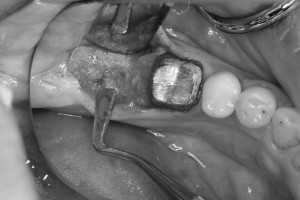

歯根膜を温存するように親知らずの抜歯を行い、

欠損部の歯肉を剥離して、

歯槽骨内に移植歯が入るスペースを形成し、

移植しました。

最後は、移植歯が動かないように、縫合糸と接着剤にて固定しています。